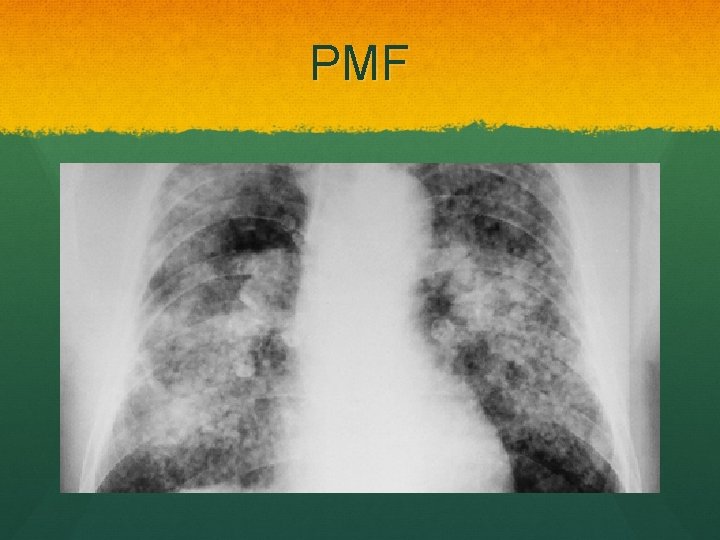

Progressive massive fibrosis Large round fibrotic nodules >10 mm Upper lobes Scarring Dyspnoea, cough, sputum May be black if cavitating lesions

PMF

PMF treatment Progresses when exposure removed Unlike simple Prognosis is poor, no treatment Coal Workers Pneumoconiosis Scheme Pneumoconiosis Workers’ Compensation Act 1979 Lump sum compensation